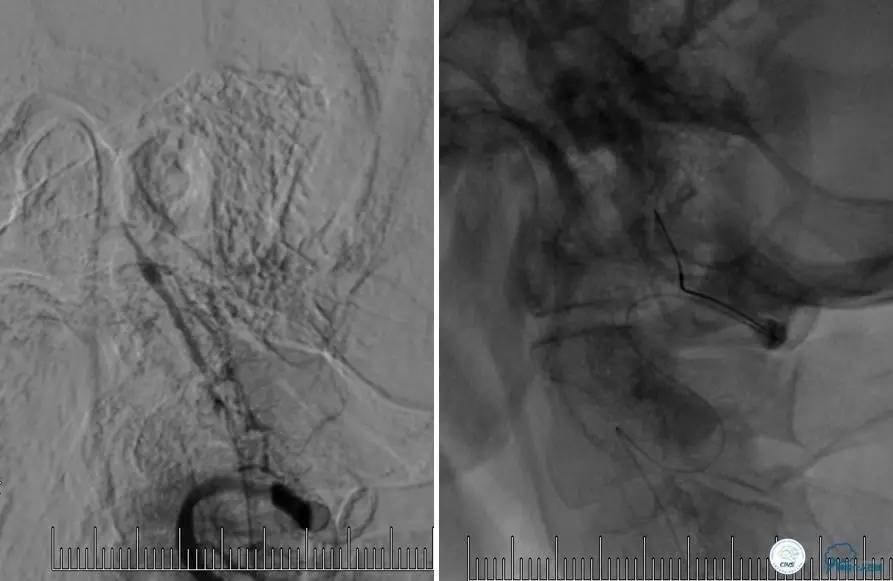

患者:58岁男性,反复头晕、肢体无力3月,当地造影见多发颅内动脉狭窄、闭塞,转来我院。

▼首先行颈动脉CTO开通术,手术顺利,Wallstent支架。

▼1周后行右侧椎动脉V4段CTO开通术。

▼微导丝穿过狭窄段,微导管造影,小球囊预扩张,2mm。

▼根据血管情况选择较大球囊再次预扩张。

▼置入2枚Wingspan支架,手术成功。

▼术后即刻CT,梗死灶内再灌注出血。

患者无症状,中性治疗。4月21日电话随访,一般情况好,当地CT示出血吸收期。